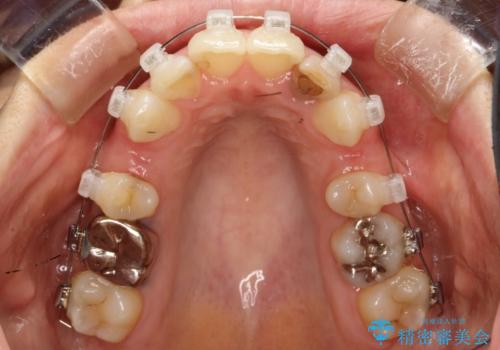

重度のガタガタと出っ歯をワイヤーによる抜歯矯正で整った歯並びへ

- 全体的ながたがたを主訴に来院されました。

上顎の前歯は前方に傾斜して、下顎の前歯は強いガタガタが見られました。

前から4番目の歯を上下左右合計2本抜歯して、歯並びを整える計画としました。

ワイヤー矯正にて治療しました。